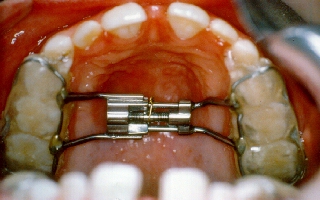

This patient had the beginnings of

crooked teeth. We now know that by utilizing modern orthodontic

techniques at as early an age as possible, many future problems can be

alleviated and in some cases even totally eliminated. For this 7 year

old girl, we used a fixed retainer called a Hyrax appliance for her

upper arch. This appliance takes advantage of the natural split in the

roof of the mouth by rapidly expanding in that area over a few short

weeks, and then allowing the bone to fill into the space over the next

few months. For the lower arch, we used a retainer called a Schwarz

appliance. The center screw in the appliance was slowly widened over

about a year's period. This changes the shape of the actual jawbone

during an active growth period. This expansion of the jawbone allows